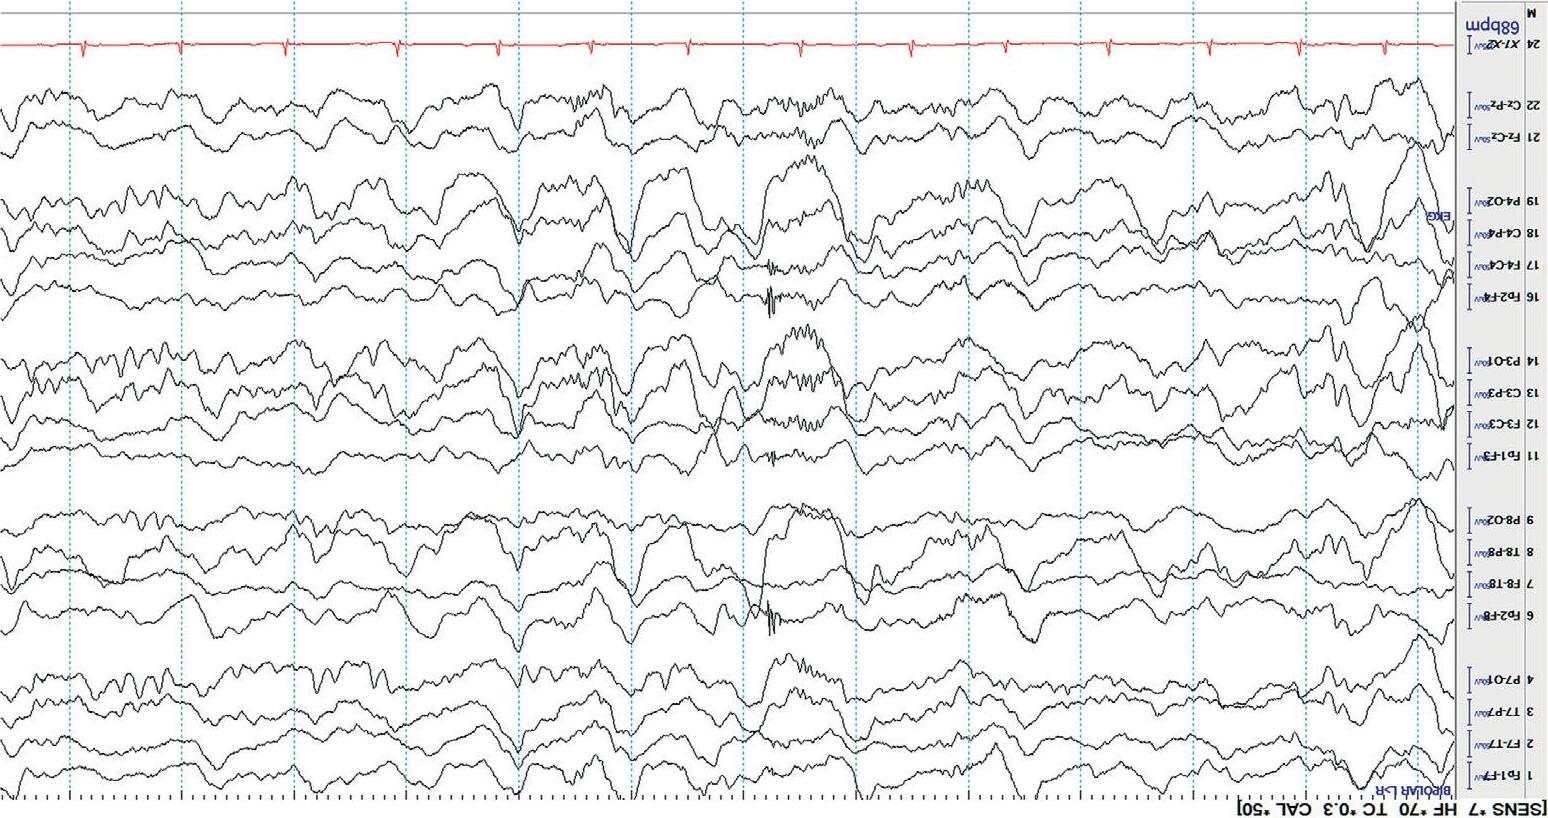

Channels(electrodepairs)aredisplayedontheEEGscreenusingspecific arrangements.Thesespecificarrangementsarecalled montages. Therearemanydifferenttypesofmontages,detaileddescriptionsofwhich arebeyondthescopeofthisbook.However,acutecareprovidersshouldbe familiarwithusingalongitudinalbipolar(doublebanana)montage,asthisisa commondefaultmontageandeasytouseatthebedside.AllEEGexamplesin thisbookusethismontage.

Eachchannelofalongitudinalbipolarmontageshowsthepotentialdifferencebetweentwoadjacentelectrodesonthescalp,andisconnectedtoother channelsinlongitudinal(fronttoback)chainsasshownbelow[3].

Figure1.3(a) showsanexampleofthelongitudinalbipolarmontage,while Figure1.3(b) showsaschematicrepresentationofitselectrodechains.

Left temporalchain Right temporalchain Left parasagittalchain Right parasagittalchain Midlinechain ECG

Figure1.3(a) EEGinlongitudinalbipolarmontage.

Display(Parameters) Atypicalbedsidedisplayusingalongitudinalbipolarmontageisshownin Figure1.3(a). Variationstothisformatexist.Commonly,theleftandtheright temporalchainsarestackedtogetherfollowedbytheleftandrightparasagittal chains.Thismakesiteasytocomparethetemporalandparasagittalregionsof bothhemispheresforasymmetry.Readersshouldknowthatthetemporal regionsarealsothemostepileptogenicsofocusingonthesechannelsyields results!Thetopbarofarecordingshowsthesensitivity,filtersettings,and timebase.